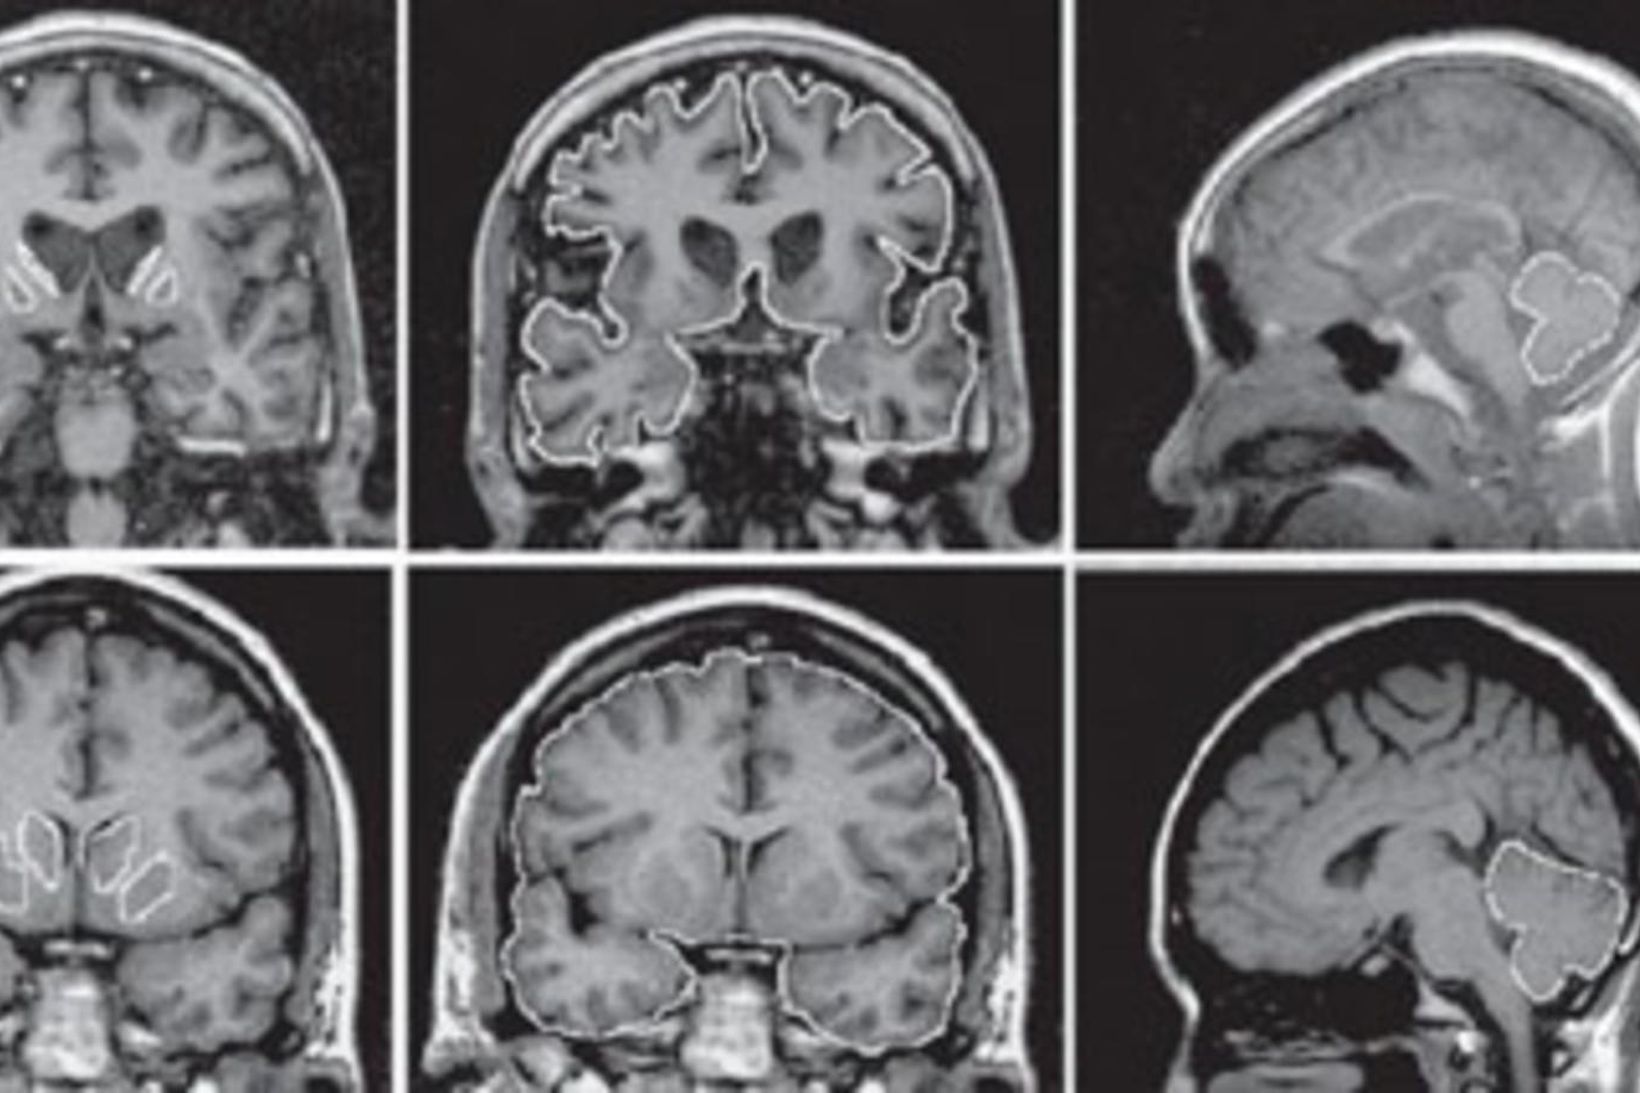

Læknum hefur í fyrsta sinn tekist að meðhöndla Huntingtonssjúkdóm (HD) með góðum árangri. HD er erfðasjúkdómur sem veldur einkennum sem minna á MND, Parkinsons og Alzheimer sjúkdómana samhliða. Samkvæmt fréttum frá Breska ríkisútvarpinu, BBC, var greint frá þessu fyrr í dag.

Vísindamenn frá University College London tilkynntu um árangurinn, þar sem þeir hafa náð að hægja á hroðrum af völdum sjúkdómsins um 75%. „Þetta þýðir að hroðnun sem venjulega myndi eiga sér stað á einu ári tekur nú fimm ár ef sjúklingurinn fer í þessa nýju meðferð. Í okkar villtustu draumum hefði okkur ekki dottið í hug að ná svona árangri,“ sagði Sarah Tabrizi, leiðandi vísindamaður í rannsóknarvinnunni, í samtali við BBC.

Meðferðin felur í sér umfangsmikla heilaskurðaðgerð þar sem erfðaefni sjúklingsins er breytt. Þó að búist sé við því að meðferðin verði dýr, gefur hún von um bætt lífsgæði fyrir þá sem glíma við sjúkdóminn. Alls tóku 29 sjúklingar, sem hafa verið greindir með sjúkdóminn, þátt í rannsókninni.

Í sumum tilfellum hafa sjúklingar farið svo vel í meðferðinni að þeir hafa snúið aftur til vinnu, sem áður var talið óhugsandi. Bandaríska lyfjafyrirtækið Uniqure, sem fjármagnaði rannsóknina, hyggst sækja um einkaleyfi fyrir meðferðinni og markaðssetja hana í byrjun næsta árs. Forsvarsmenn fyrirtækisins telja þó ólíklegt að meðferðin verði aðgengileg öllum, þar sem hún krefst skurðaðgerðar sem ekki er á allra færi að framkvæma.

Rannsóknarteymið hefur nú hafið nýja rannsókn þar sem reynt verður að koma í veg fyrir sjúkdóminn hjá einstaklingum sem bera genið án þess að hafa byrjað að finna fyrir einkennum sjúkdómsins.